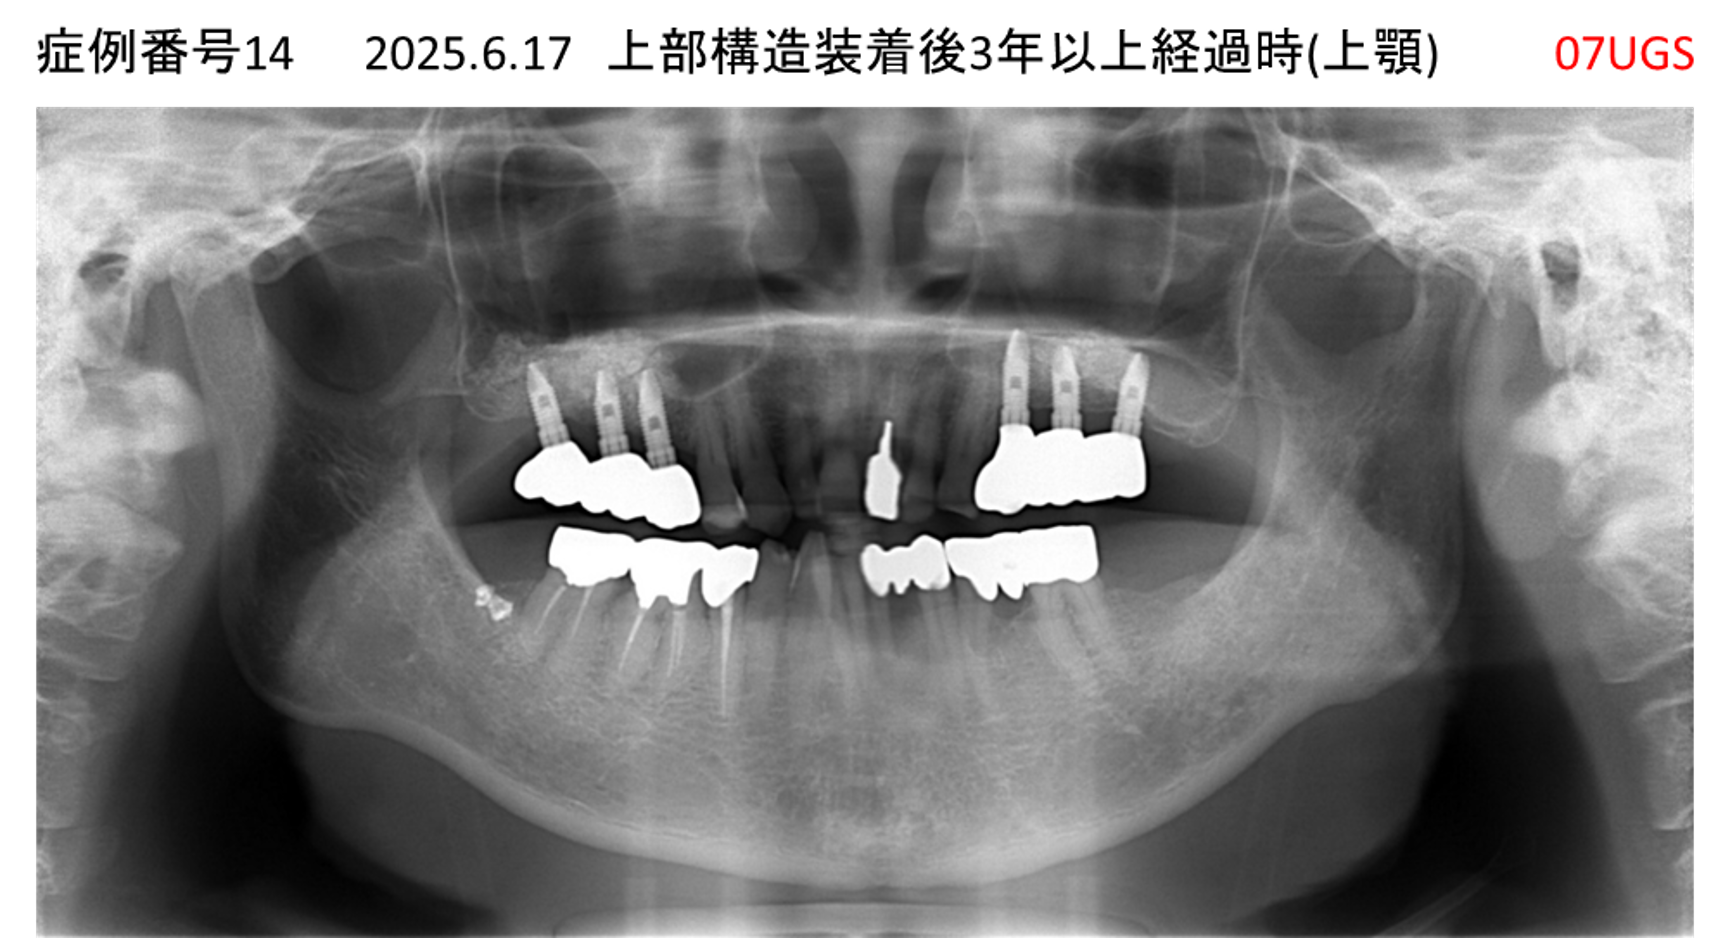

全く噛めない患者様のインプラント症例

| 治療名称 |

インプラントAGC |

| 治療費用 |

860万円+税 |

| 治療期間 |

12か月 |

| 患者さんの症状(主訴) |

全く噛めない、ごはんが後もに食べられるようになりたい、人前で口元を隠したくない |

| 治療内容 |

サイナスリフト、GBR、インプラント、AGC |

| 治療結果 |

しっかり噛めて踏ん張ることができる。食べ物をを選ばなくて済む、何でも食べられる、体重が増えた。見栄えがきれいすぎて自分じゃないみたい |

| 治療の注意点(リスク/副作用) |

インプラントが壊れたら再治療が必要 |